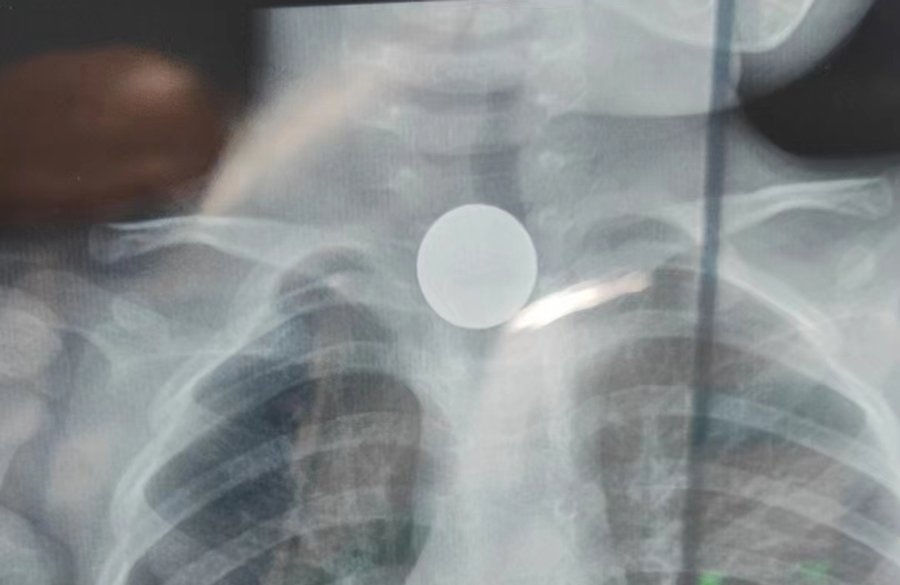

了解了患儿的情况后,国家儿童医学中心、首都医科大学附属北京儿童医院耳鼻喉头颈外科常驻专家、a片网站 副院长张薇仔细看了患儿的X光片,明确了异物的存在和准确位置。由于异物存留时间长,食道是否有肉芽增生、有无穿孔等情况都不明确,张薇副院长决定采用全麻下通过食道镜直视下行异物取除术。

手术非常顺利,当卡在小强食道入口下方的硬币被取出后,家长才知道,原来导致孩子受罪一个多月的竟是一枚硬币。由于硬币卡在食道内时间太长,被取出时颜色已经发黑。术后,小强不能像其他孩子一样迅速恢复呼吸,而是住进了ICU。原来是由于异物坎顿,食道入口关闭不全,小强进食时总会呛咳,导致反复吸入性肺炎,肺功能明显受损,肺内通气量不足、反复发热,全身身体机能下降,所以不能及时苏醒。不过,经过医务人员进一步治疗后,小强现已康复出院。